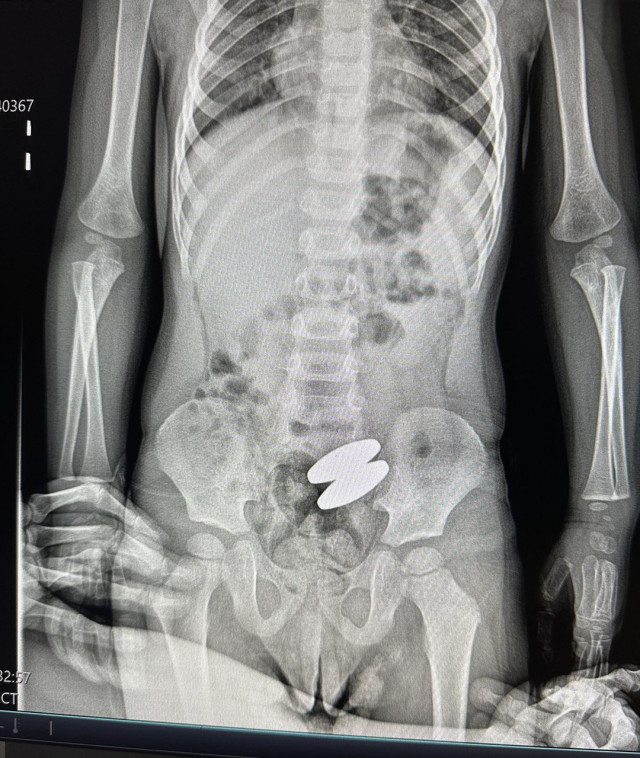

Два магніти досить великого розміру лікарі Волинського обласного медоб’єднання захисту материнства і дитинства вилучили із кишківника 2-річного хлопчика.

«Я перевірила батарейки в іграшках та інші деталі. В лікарні у Володимирі, куди ми звернулися спочатку, я наголосила, що підозрюю проковтування стороннього предмету. Зробили рентген і вже на рентгені я побачила саме ті магніти з холодильника», – розповіла жінка.Читати ще: Термометр опинився у товстій кишці: на Волині госпіталізували піврічну дитину

Хірург Василь Никитюк, який лапаросокопічно прооперував хлопчика, наголосив, що ці магніти великі й важкі, тож природньо б не вийшли. На момент операції магніти були з’єднані між собою, тисли на стінки кишківника, внаслідок чого в ділянках тиску припинилося кровопостачання – без оперативного втручання це загрожувало перфорацією.Після операції хлопчик почувається добре, на щастя, вдалося уникнути важких ускладнень для його здоров’я.